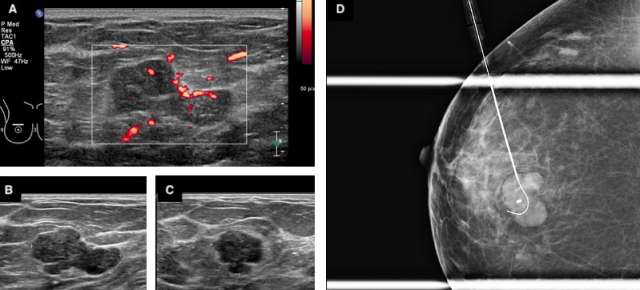

Certain imaging features that may help differentiate a phyllodes tumor from a fibroadenoma include size greater than 3 cm, irregular shape, microlobulated margins, complex heterogeneous echogenicity and internal hypervascularity.2,3 Phyllodes tumors may also be of higher density on mammography given their larger size at presentation.2 On MRI, phyllodes tumors are more likely to demonstrate heterogenous enhancement with internal cystic areas.2 When internal cystic areas are present, phyllodes tumors may demonstrate posterior acoustic enhancement on sonography.

As such, the recommended management for phyllodes tumors is surgical excision. Even when benign, phyllodes tumors carry up to a 25% chance of local recurrence after excision.1 Surgical excision with wide margins or even mastectomy for very large tumors may be necessary.